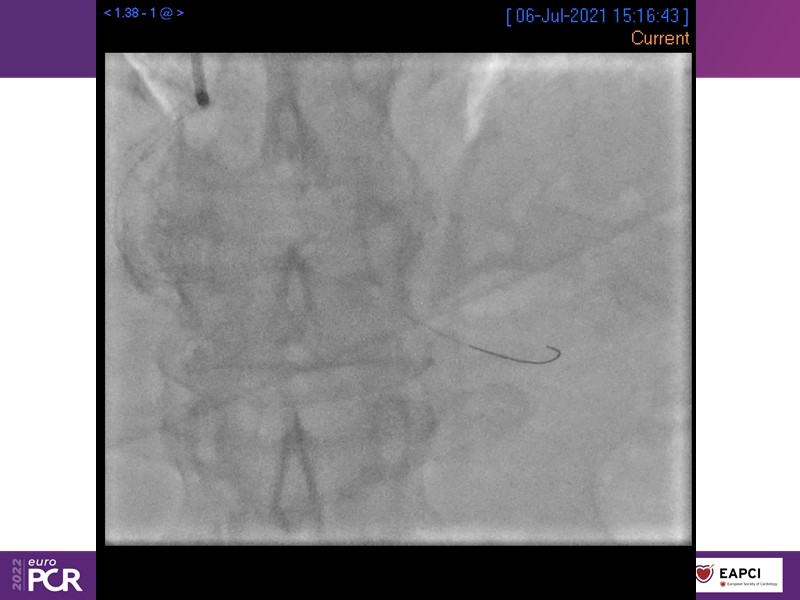

Alexandre Abizaid, Marco Valgimigli, Fazila Malik, Luca Testa, Patrick W. Serruys, Damiano Regazzoli, Kumar Prathap, and Sandeep Basavarajaiah take turns in this session to discuss two innovative technologies: a stent platform with nanotechnology and a novel drug-coated balloon (DCB). These novel technologies both have unique features that could change daily practice and improve outcomes.

- To find out more about the application and mechanism of a sirolimus coated balloon for coronary artery disease treatment with case presentations in complex settings

- To understand how useful is a DES and DCB stent platform in complex coronary artery disease settings with case demonstrations and follow-up in diabetes mellitus